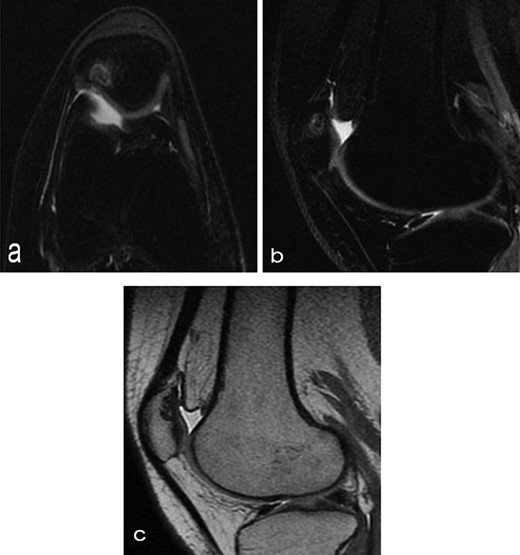

A 14-year-old female dancer presented with increasing right knee pain and functional disability without any trauma. Her pain was retropatellar pain that often radiated medially or laterally from the patella, exacerbated by climbing stairs, running and squatting. She was unable to perform any sports activities. Examination revealed peripatellar tenderness and crepitus, full range of motion and the knee was stable. Radiological examination included both MRI and computed tomography of the knee were performed at the beginning. MRI showed osteochondritis dissecans at the area at the superolateral facet of the patella in the deep subchondral area as shown in Fig. 1. This was appropriately treated conservatively with 6 months of reduced load and protected weight bearing without relief of symptoms. She quit sport activity for 2 years and then another MRI was performed Fig. 2. After 2 years we opted for adipose-derived mesenchymal stromal cells (AD-MSCs) intra-articular therapy according to the procedure described by Tremolada et al. [9]. The patient’s parents were given written information regarding the use of AD-MSCs therapy, including relative risks of this therapy and also relevant treatment alternatives that could otherwise be explored. Postoperative radiological evaluation was performed at 6 months and 12 months after AD-MSCs procedure as shown in Figs. 3 and 4. Postoperative clinical evaluation was performed using IDKC, Lysholm and Tegner scores (Table 1). After surgery, patients began a McConnell program of lateral retinacular stretching, patellar taping and vastus medialis obliquus muscle exercises. The patient was encouraged to swim and cycle to reduce impact loading. Using AD-MSC, she reported a complete relief of pain after 1 year from the procedure. Routine MRI follow-up 2 years later showed evidence of appreciable improvement in cartilage volume and osteochondral architecture at the site of injury. Early MRI T2 mapping at 6 months indicated that the area of cartilage regeneration exhibited high water content suggestive of immature cartilage or fibrocartilage morphology. Later T2 mapping at 18 months after the procedure, indicated progressive maturation of cartilage from deep to superficial layers with more hyaline like cartilage morphology. Limitations of the study are lack of arthroscopic intra-articular visualization and classification of the patella lesion.

Radiographs of the patient’s knee at 14 years old (a) Axial T2-weighted MRI sequences (b) sagital T2-weighted MRI sequences showed abnormality area at the superolateral facet of the patella in the deep subchondral area, this area of altered signal, hypointense in T1 and hyperintense in T2 with a shaded surrounding edema, was oval in morphology and had a craniocaudal extension of about 12 mm and transversal about 10 mm, the lesion interrupted the corresponding patellar articular cartilage which appears swollen in this position (c) axial computed tomography scan showed loss bone at that same point of patella in the right knee.